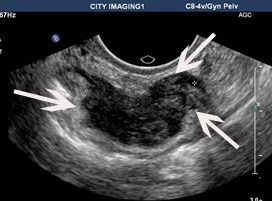

The larger the lesion, the easier it is to see on ultrasound, but in the hands of experienced imaging specialists lesions of only a few millimetres may be diagnosed. Endometriosis lesions on ultrasound look darker (seen as blacker) on ultrasound.

The left image shows a small lesion on the back of the vagina, causing pain with sexual intercourse. The right image shows a large bowel lesion, which seems very easy to see, but unless the bowel is inspected, it is not noticed on routine pelvic ultrasound.